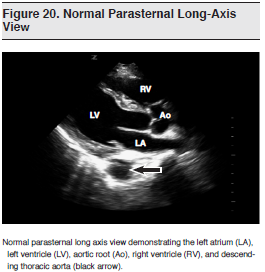

Emergency echocardiography is a core application of emergency ultrasound and is a key element of the FAST examination.1,176,177 Although comprehending image orientation178 and acquiring images can be somewhat challenging, emergency echocardiography has had a major impact on emergency clinicians’ ability to detect cardiac abnormalities and on patient care and can be life-saving.179 (See Figure 20.) It provides emergency clinicians with time-sensitive anatomic and physiologic information in a variety of cardiac-related scenarios, including cardiac arrest, unexplained hypotension, syncope, shortness of breath, and chest pain.180-183 Emergency echocardiography can help risk-stratify patients in the ED and further guide resuscitative efforts.184,185 At times, the information and disorders noted on focused cardiac ultrasound are vast and may surpass what the emergency clinician is able to appreciate and integrate. As per the American Society of Echocardiography (ASE)/ACEP Consensus Statement, the ability to assess global left ventricular function and detect pericardial effusions and right heart dilatation (chamber sizes) are within the scope of emergency clinicians and can help answer critical patient management questions.186,187